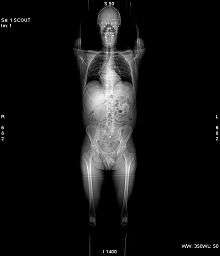

A CT scan makes use of computer-processed combinations of many X-ray images taken from different angles to produce cross-sectional (tomographic) images (virtual "slices") of specific areas of a scanned object, allowing the user to see inside the object without cutting.

Digital geometry processing is used to generate a three-dimensional image of the inside of the object from a large series of two-dimensional radiographic images taken around a single axis of rotation.[2] Medical imaging is the most common application of X-ray CT. Its cross-sectional images are used for diagnostic and therapeutic purposes in various medical disciplines.[3] The rest of this article discusses medical-imaging X-ray CT; industrial applications of X-ray CT are discussed at industrial computed tomography scanning.

CT produces a volume of data that can be manipulated in order to demonstrate various bodily structures based on their ability to block the X-ray beam. Although, historically, the images generated were in the axial or transverse plane, perpendicular to the long axis of the body, modern scanners allow this volume of data to be reformatted in various planes or even as volumetric (3D) representations of structures. Although most common in medicine, CT is also used in other fields, such as nondestructive materials testing. Another example is archaeological uses such as imaging the contents of sarcophagi. Individuals responsible for performing CT exams are called radiographers or radiologic technologists.[4][5]